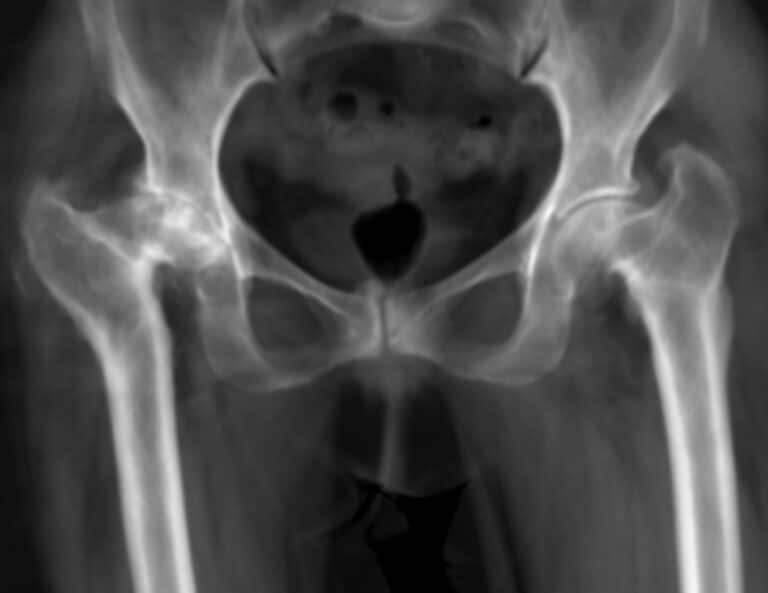

Radiographs frequently show sequelae of previous pelvic or femoral surgeries, along with a markedly asymmetric hip architecture.

When hip replacement is indicated, 2D planning is insufficient. It does not accurately reflect the true anatomy, particularly in the axial plane, nor the acetabular orientation, femoral anteversion, or retroversion.

A 3D CT scan is essential. It provides true-to-size analysis, three-dimensional reconstruction of the hip morphology, and evaluation of muscle trophicity (gluteal muscles, psoas). The presence of fatty degeneration is a poor prognostic factor for functional recovery.

In addition, a standing EOS scan helps evaluate lumbopelvic–femoral balance and lower-limb alignment abnormalities.